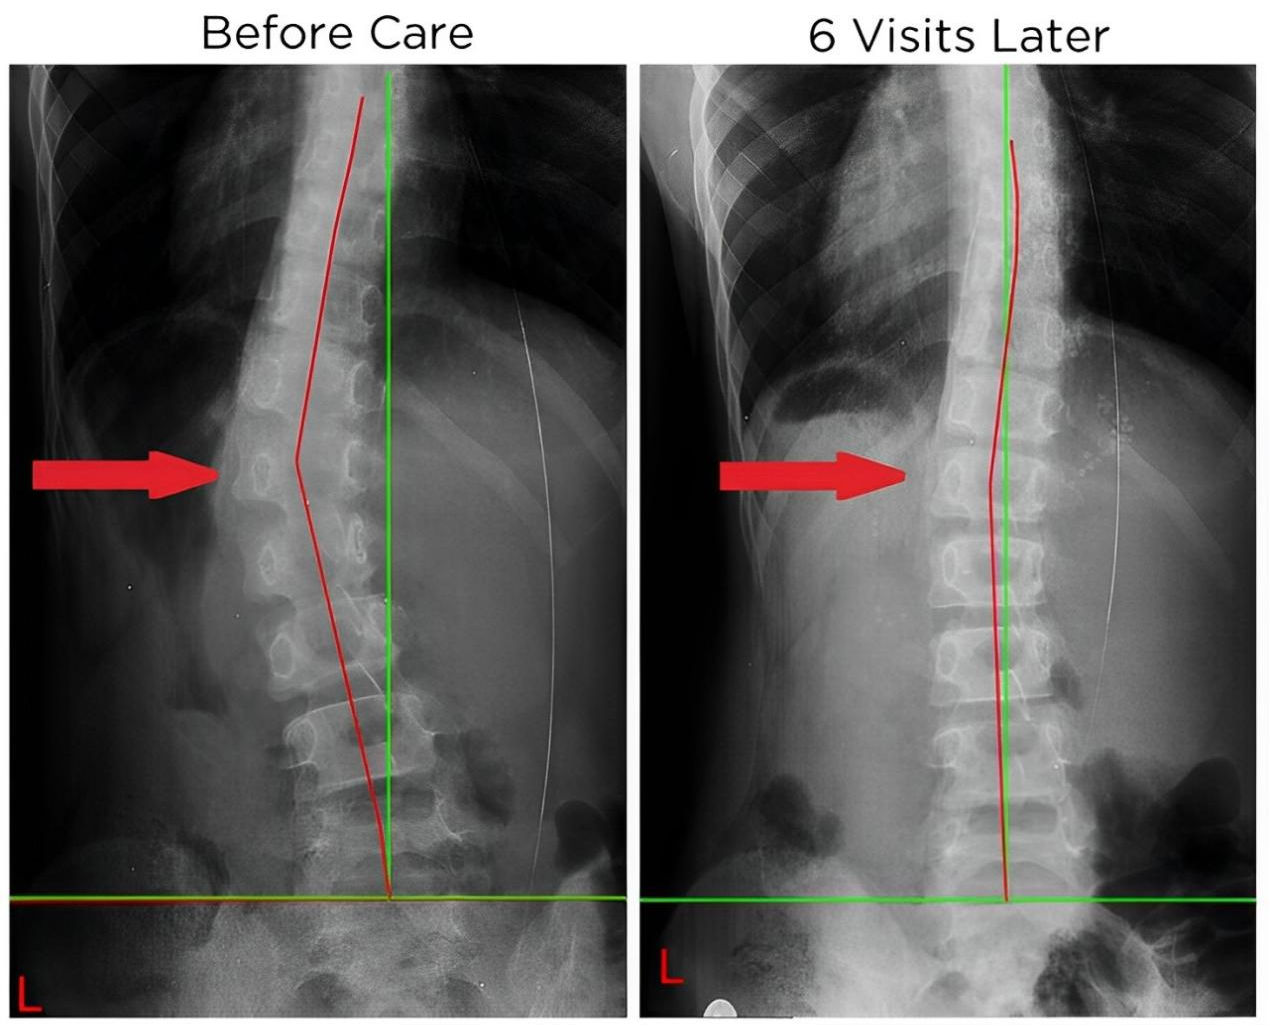

四、 恢復脊椎自然曲度

五、矯正完和矯正后的對比案例: